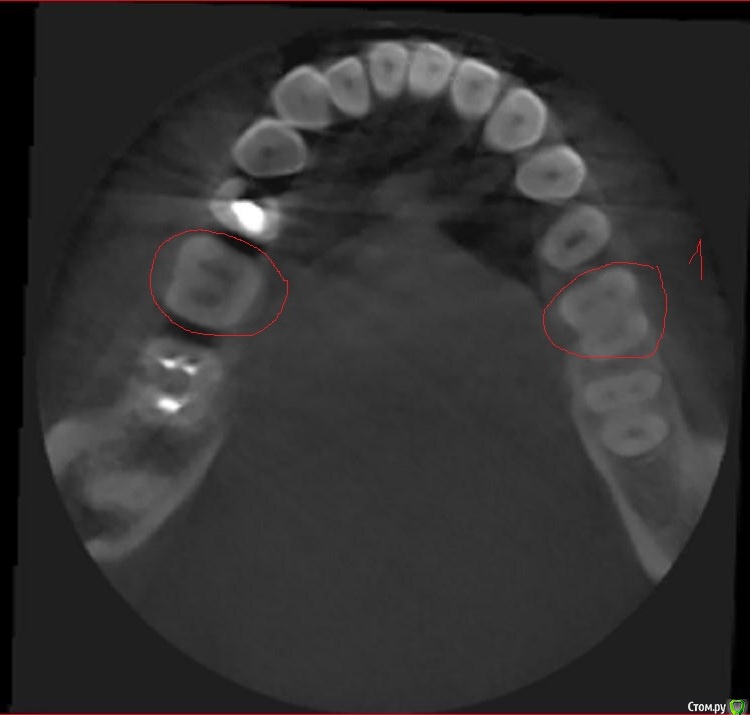

Svetic Опубликовано 16 августа, 2015 Поделиться Опубликовано 16 августа, 2015 (изменено) Здравствуйте, история такая. Отправилась лечить нижнюю шестерку. Выпала пломба, зуб реагировал на холодное и на накусываение. Врач поставила пломбу,депульпировать не стала. Зуб заболел через два дня. Четыре дня назад удалили нерв, реакция зуба на холодное осталась. Позвонила по телефону врачу, говорит что после мышьяка болеть зуб не может. Мог ли врач пропустить один канал? Нашла томограму которую делала 3 месяца назад. Скажите пожалуйста сколько в шестерках каналов? Врач пролечила 3 канала. Тот зуб под номером 1 еще до лечения. Изменено 16 августа, 2015 пользователем Svetic Ссылка на комментарий

St. Опубликовано 16 августа, 2015 Поделиться Опубликовано 16 августа, 2015 Каналов 4. КТ доктор во время лечения видел? Ссылка на комментарий

St. Опубликовано 17 августа, 2015 Поделиться Опубликовано 17 августа, 2015 Искать и долечивать пропущенный канал. Ссылка на комментарий